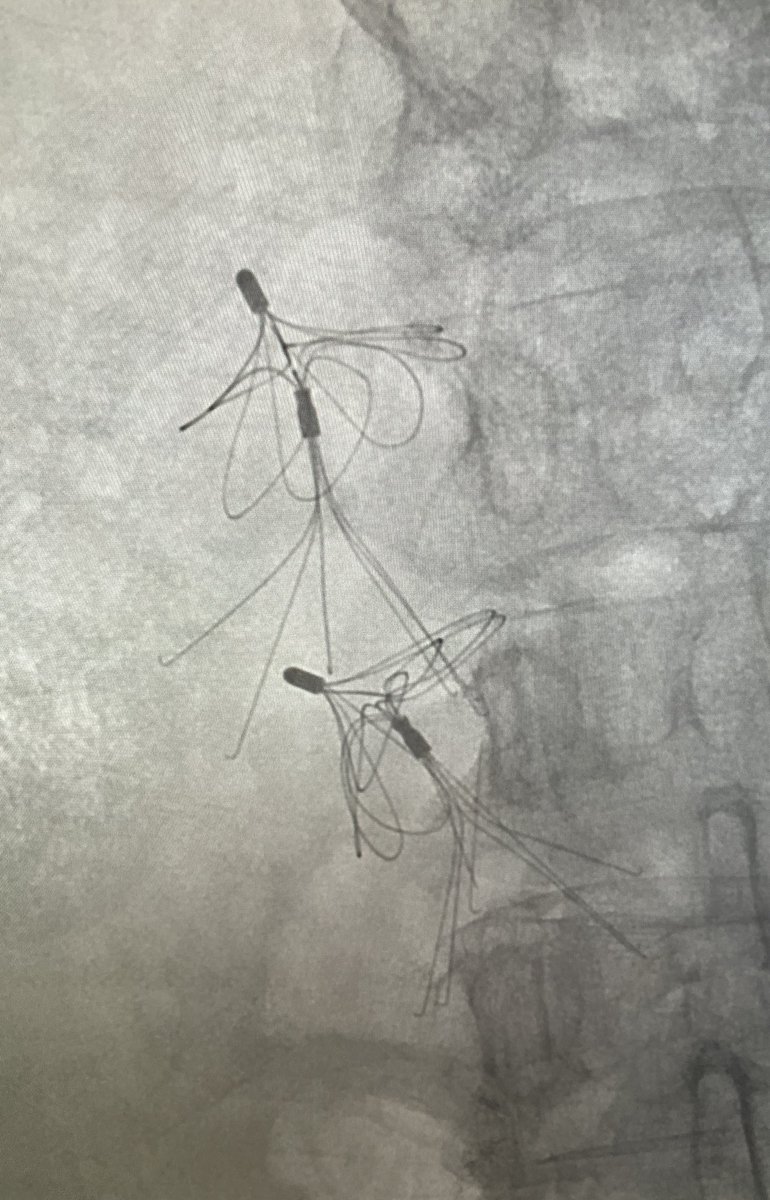

@bimada808

Brian Imada

3 years

Option Elite filter in since February 2021 initially failed loop snare and forceps techniques, taken out with @PhilipsHealth #CavaClear laser sheath. 9 seconds of laser time. Great experience! #filterout @IrColorado @pj_rochon